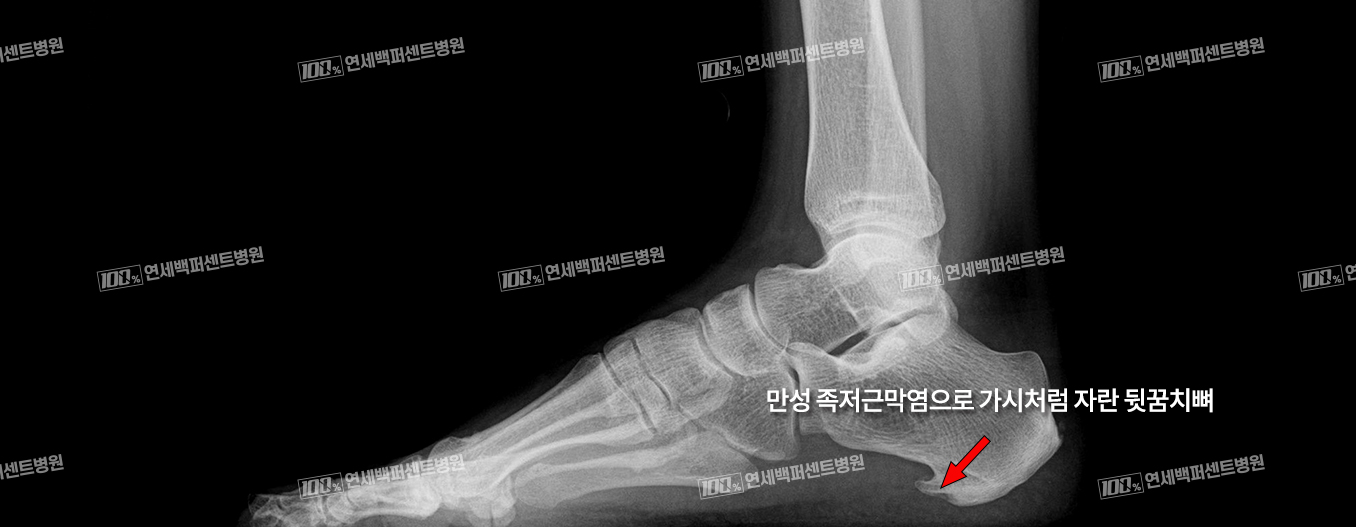

족저근막은 뛰거나 걸을 때 발바닥에 가해지는 충격을 흡수하는 역할을 합니다.

이 족저근막에 이상이 생겨 발바닥에 통증이 생기는 질환을 족저근막염이라고 합니다.

하이힐, 플랫슈즈 등 발에 부담을 주는 신발 착용, 급격한 체중증가, 무리한 운동, 퇴행성 변화 등의 원인으로 발생합니다.